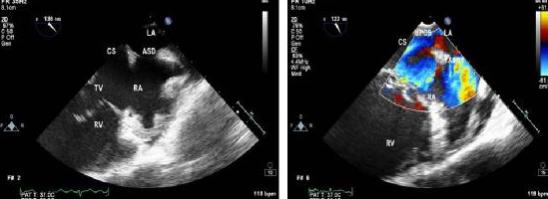

3、超声心动图检查可显示房缺的位置和大小,这是诊断房缺的有力证据。

5.原发孔未闭与继发孔未闭的临床表现极为相似。房缺患者心尖部闻及反流性收缩期杂音,心电轴左偏,P-R间期延长或伴不完全性右束支传导阻滞,应高度怀疑原发孔未闭。二维超声或右心导管检查示缺损的部位较低,接近三尖瓣口附近。右心房血氧含量增高,右心室更高,多普勒彩超或心血管造影可明确房室通道或二尖瓣关闭不全等改变。

(5)单心房:房间隔完全缺如,左右心房不分,血液混合,多有轻度发绀。临床表现与完全性心内膜垫缺损相似。心导管检查左心房、右心房、双心室、肺动脉、主动脉血氧浓度几乎相等。多普勒彩超和心血管造影可助诊断。